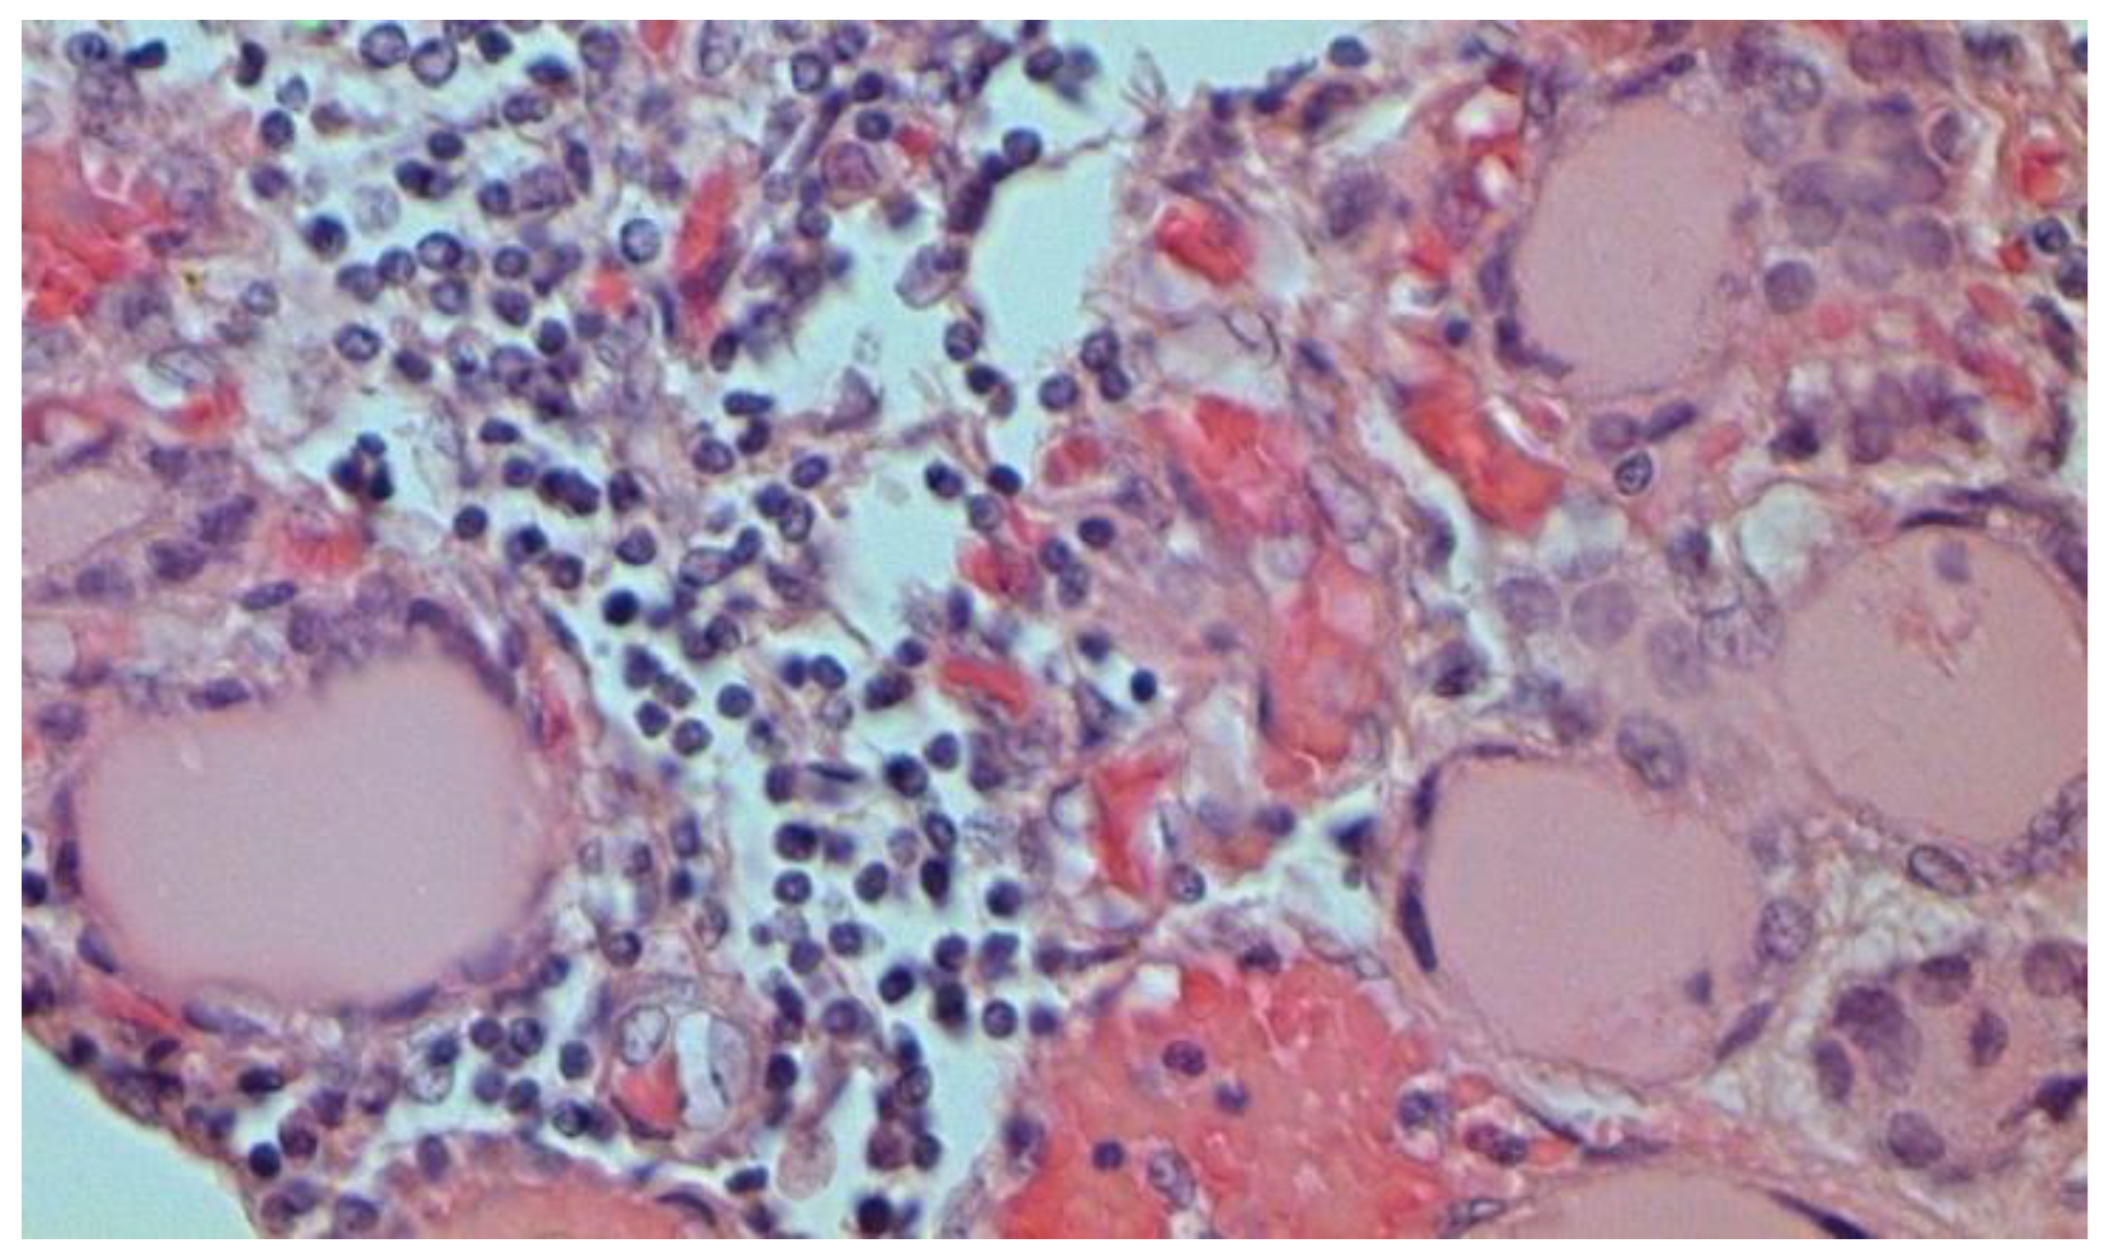

The main morphological substrate of respiratory insufficiency is diffuse alveolar damage. The term viral pneumonia, widely used in the clinic, essentially reflects its development. In turn, severe diffuse alveolar injury is synonymous with the clinical concept of “acute respiratory distress syndrome” (ARDS). In the pathogenesis of ARDS, without a doubt, the most important role is played by the damage to the microcirculatory bed, the genesis of which requires further study, but direct viral damage is most likely. COVID- 19 is characterized by a pronounced fullness of the capillaries of the interalveolar septa, as well as branches of the pulmonary arteries and veins, with erythrocyte sludge, fresh fibrin, organizing blood clots, and intrabronchial, intrabronchiolar, and intra-alveolar hemorrhages, which are a substrate for hemoptysis, as well as perivascular hemorrhages (Figure 8). Pronounced alveolar hemorrhagic syndrome is characteristic of most cases, up to the formation, in fact, of hemorrhagic infarcts (although true hemorrhagic infarcts are not uncommon). Pulmonary blood clots are important to distinguish from thromboembolism, as pulmonary embolism (PE) is also characteristic of COVID-19. Thrombosis of the pulmonary arteries sometimes progresses to the right parts of the heart, and thrombosis of the arteries of various organs with the development of their infarcts (myocardium, brain, intestines, kidneys, and spleen) is described. This distinguishes changes in the lungs in COVID-19 from those previously observed in influenza A/H1N1. Despite the pronounced hemorrhagic syndrome, significant deposits of hemosiderin are not observed.

Figure 8.

Edema and perivascular hemorrhages in lung. H-E ×100.

The dynamics of changes in ARDS associated with COVID-19 can only be judged by analogy with SARS and influenza A/H1N1pdm. In the late (productive) stage (after 7–8 days or more from the onset of the disease) of diffuse alveolar damage, macroscopically the lungs are enlarged, low-air, dense, fleshy, and can resemble the density of the liver, sometimes with diffuse whitish layers and areas of different sizes. Microscopically, siderophages, a relatively (in comparison with swine influenza) small number of hyaline membranes (Figure 9), fibrin, squamous metaplasia of the bronchial, and bronchiolar and alveolar epithelium can be detected in the lumens of the alveoli, respiratory and terminal bronchioles, the thickening of the interalveolar septa due to sclerosis, lymphoid (mostly CD3+ and CD 8+) (Figure 10 and Figure 11) and macrophage (Figure 12) infiltration, and the proliferation of type II alveolocytes. The nature of cytoproliferative changes of the epithelium in the trachea and bronchi remains unclear. In the final stage of the disease, sections of fibrous tissue may develop in all parts of the lungs (usually in the lower lobes) (Figure 13), which contributes to the development of chronic respiratory failure. It is notable that near the overgrowth of collagen fibers in the lungs, neoangiogenesis is also typical (Figure 14). The electron microscopic study revealed changed viral particles (Figure 15).

Figure 9.

Hyaline membranes (arrows) in lung. H-E ×100.